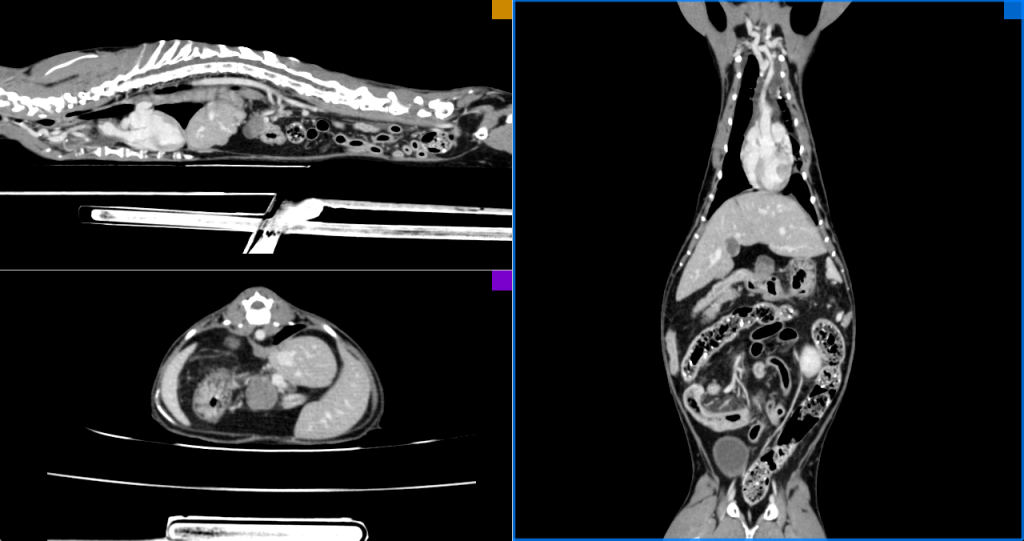

Спустя 6 месяцев с момента проведения компьютерной томографии в момент обращения была проведена контрольная неселективная КТ-ангиография (рис. 4).

Перед каждой процедурой дачи ломустина проводился общий клинический анализ крови, а также осуществлялся постоянный ультразвуковой контроль брюшной полости для мониторинга рецидива и при необходимости – в случае ухудшения аппетита или других нарушений общего состояния пациента. При появлении негативных реакций со стороны организма, связанных с противоопухолевой терапией, также осуществлялся ультразвуковой мониторинг и дополнительно проводился ОАК. Контрольное рентгенологическое исследование не проводилось. Спустя 6 месяцев после начала терапии (в состоянии клинической ремиссии и полного клинического ответа) было выполнено контрольное КТ-исследование.